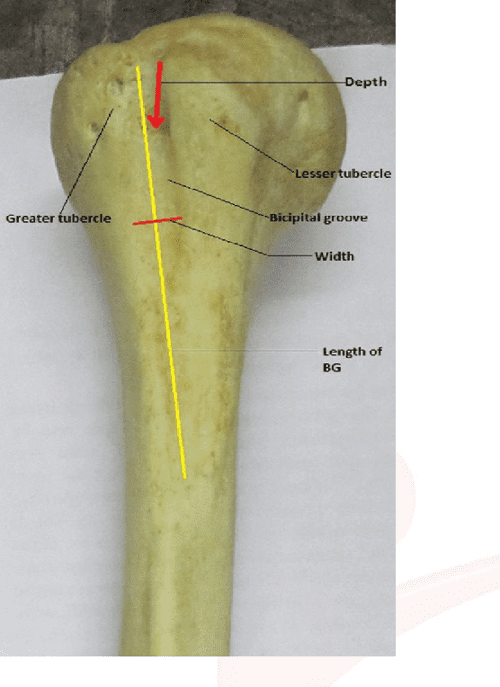

From www.semanticscholar.org

Figure 1 from MORPHOMETRIC ANALYSIS OF BICIPITAL GROOVE OF HUMERUS WITH What Is Another Name For A Bicipital Groove The bicipital groove, a deep groove on the humerus also referred to as the intertubercular groove or sulcus intertubercular, separates the greater and lesser tubercles. The intertubercular sulcus, also known as the intertubercular groove, or bicipital groove, is a groove separating the greater and lesser tubercles of the humerus. It is sometimes referred to as the bicipital groove. The intertubercular. What Is Another Name For A Bicipital Groove.

From www.researchgate.net

Location of measurement landmarks in relation to the long head of the What Is Another Name For A Bicipital Groove The intertubercular sulcus (intertubercular groove or bicipital groove) is the vertical, longitudinal depression found on the anterolateral aspect of the proximal end of the humerus. The long tendon of the biceps brachii and an. The meaning of bicipital groove is a furrow on the upper part of the humerus occupied by the long head of the biceps —called also. The. What Is Another Name For A Bicipital Groove.